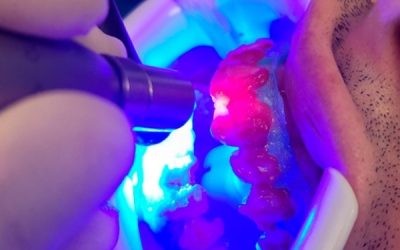

Grazie ai molteplici progressi nella tecnologia e nei materiali utilizzati, la conservativa dentale permette di curare i denti danneggiati, riducendo al minimo la rimozione della struttura dentale originale. Presso il nostro studio dentistico, siamo specializzati...

Conservativa